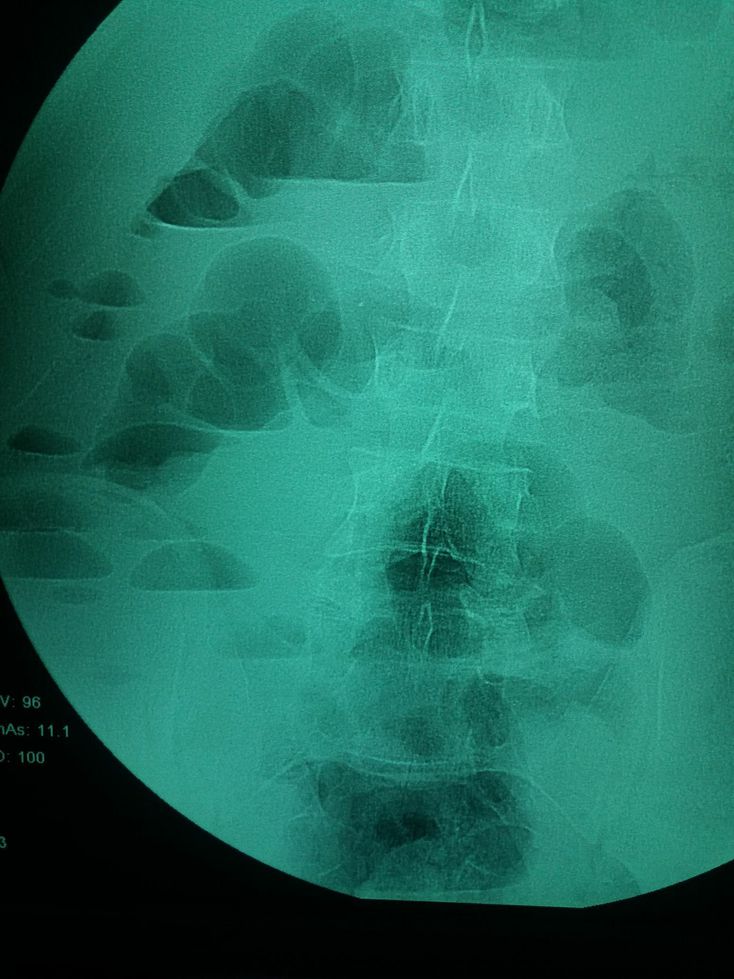

What do you see

Surgery

I wanna say diverticulosis but not completely sure

Air fluid levels